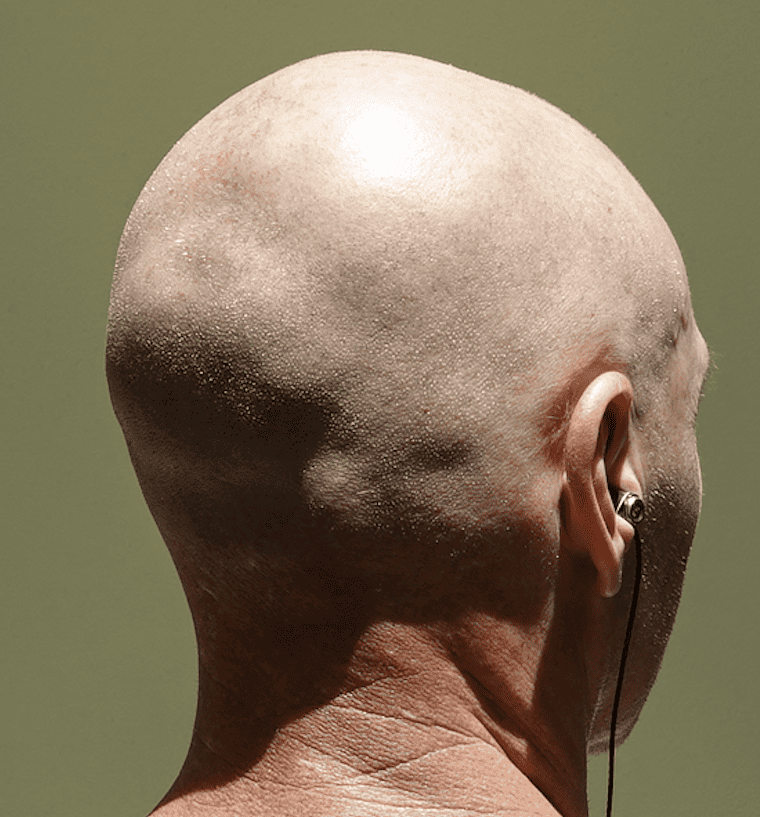

Desire for less prominent protrusion on the back of the head.

Occipital skull reduction through a bone burring technique.

Desire for less prominent protrusion on the back of the head.

Occipital skull reduction through a bone burring technique.